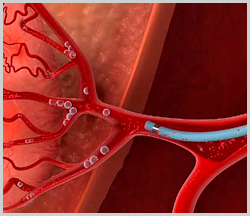

Хирургические процессы при эмболизации гемангиомы на фото

Раздел: Снимки-откровения